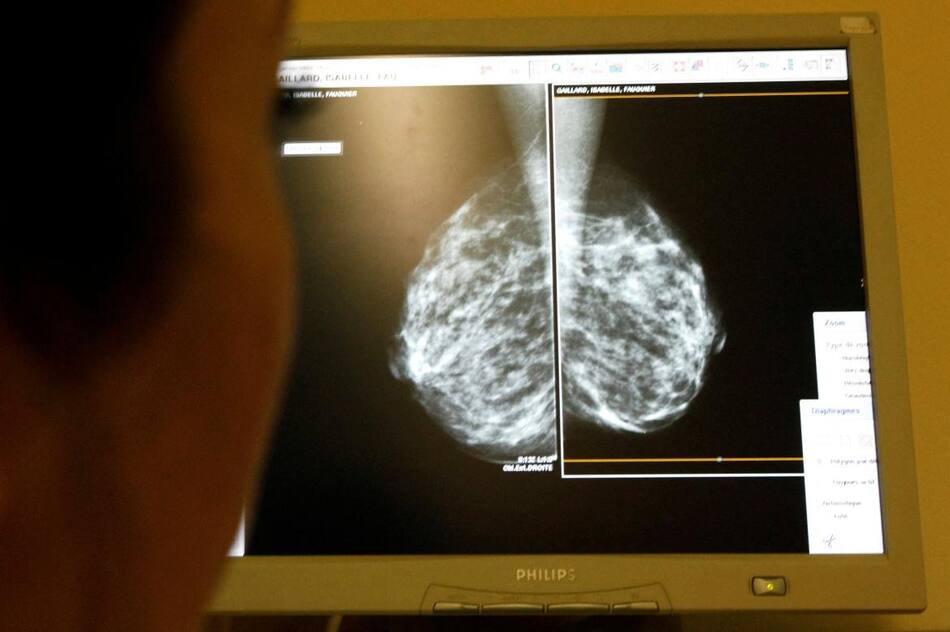

Por otra parte, es fundamental la realización de una mamografía, que permite ver lo que aún no se puede tocar. Se recomienda realizarla anualmente a partir de los 40 años a todas aquellas mujeres asintomáticas, con estudios clínicos normales y sin antecedentes de la enfermedad, y en las pacientes con antecedentes de cáncer de mama en familiares de primer grado, se recomienda hacerla 10 años antes de la edad de detección del cáncer del familiar más cercano. Si se detecta el tumor en esta instancia temprana, la enfermedad alcanza su máximo nivel de curación.

8. ¿La mamografía es dolorosa? No. Algunas mujeres con mamas sensibles pueden experimentar incomodidad, pero no dolor.

9. ¿La mamografía produce cáncer? Las dosis de radiación que se utilizan en una mamografía son muy bajas y no producen cáncer de mama ni de otro órgano. Si bien es cierto que la mamografía utiliza rayos, las dosis que se usan cuando la mamografía se realiza con un mamógrafo de última generación son sumamente bajas: es equivalente a la dosis efectiva de radiación que cualquier persona recibe por la radiación ambiente en el transcurso de un mes.